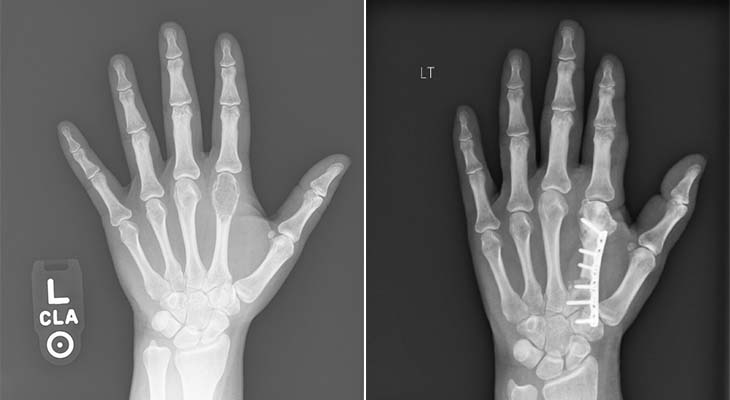

X-rays

X-rays are a type of medical imaging test that uses a small dose of ionizing radiation to create pictures of structures inside the body. Dense materials like bone or tumors appear white, while softer tissues show up in shades of gray or black.

Use low-dose radiation to create images of the inside of the body.

- Quick and painless

- Used to detect tumors in bones and chest

- Often the first test performed